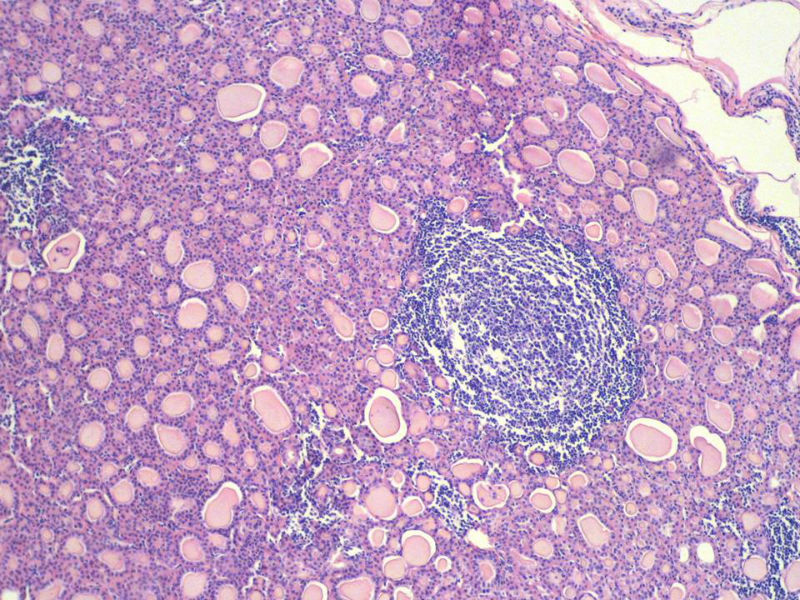

女,60岁,右侧甲状腺肿物两个月,术中见肿块与周围组织无粘连,肉眼,灰红色组织,3X2X2厘米,切面见一直径2.5厘米肿物,包膜完整,灰黄色,质软。

右侧甲状腺肿物图2

名称:图2

具有桥本氏病的大部分特征,有结节形成,此情况有称之为“结节性桥本甲状腺炎”